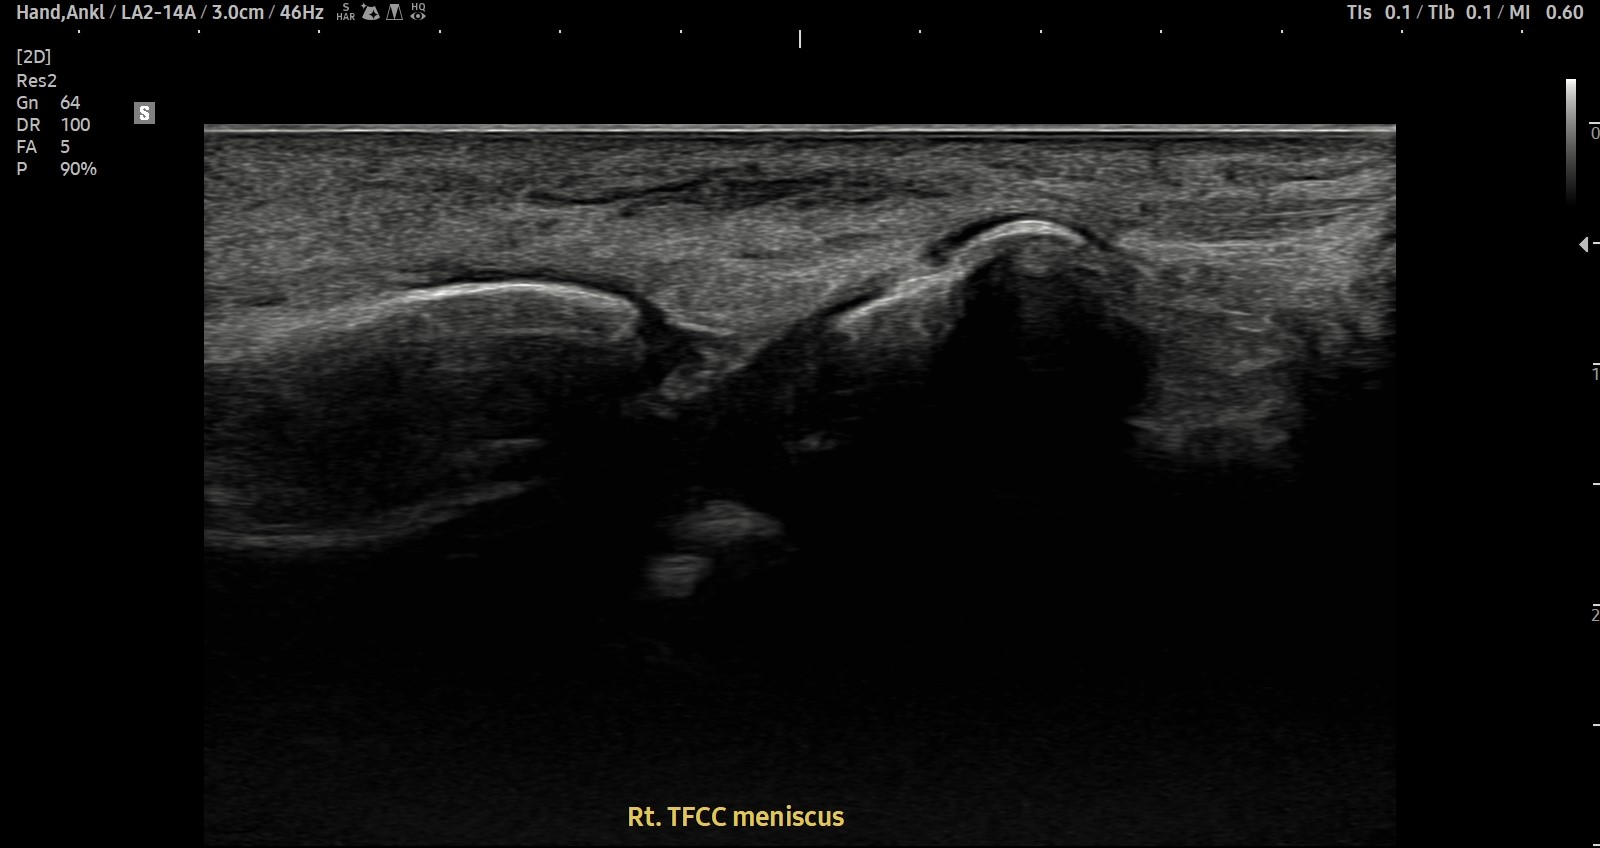

- 치료기간 : 25. 04 . 12 ~ 25 . 07 .14

- 치료횟수 : 3cycle (15회)

[치료 전]

[치료 후]